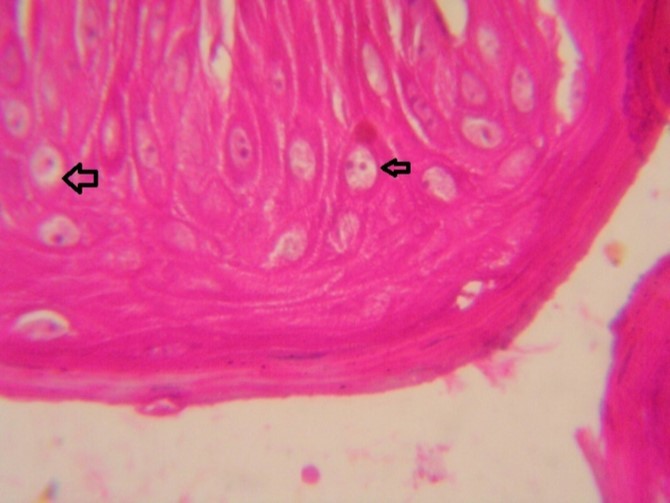

Figure 9.Tongue (dead cattle less than 1 year old) showed vesicular nuclei of stratum corium epithelium which suffering hydropic degeneration. Esinophlic intranuclear inclusions were seen surrounded by hallow zone(arrows). (Hematoxylin and fuchsin X 60)